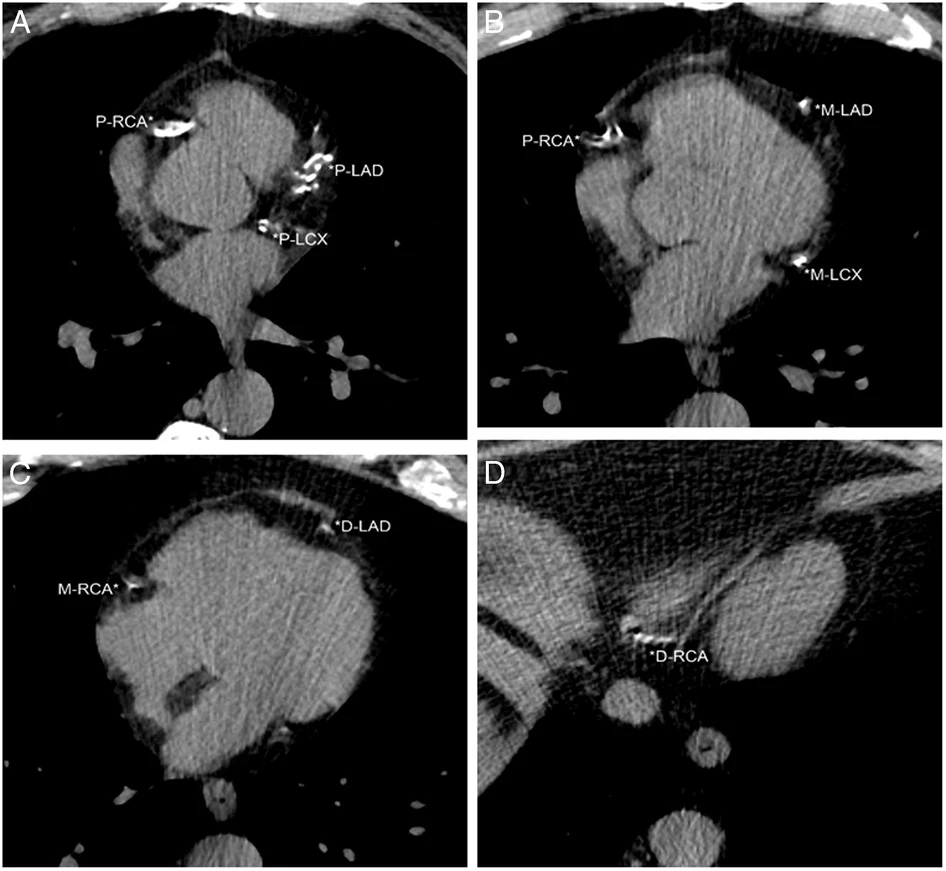

Since the heart is fully visualized on these screens, cardiovascular health is rife with opportunity. Indeed, AI software can automate the detection and scoring of coronary artery calcification from CT scans, potentially enabling earlier and more accurate identification of individuals at risk for heart disease.

The heart is fully visualized on LDCT screenings for lung cancer, making it suitable for cardiovascular assessments. Dr. Henschke's team developed a visual assessment of coronary artery calcifications (CACs) for LDCT scans that provided a 12-point score by assessing each of the four coronary arteries. In this figure, the patient had an ordinal CAC score of 8 based on calcifications in the proximal left anterior descending (P-LAD), proximal left circumflex (P-LCX), and proximal right coronary arteries (P-RCA) on A, mid left anterior descending (M-LAD) and mid left circumflex (M-LCX) coronary arteries on B, distal left anterior descending (D-LAD) and mid right coronary arteries (M-RCA) on C, and distal right coronary artery (*D-RCA) on D.